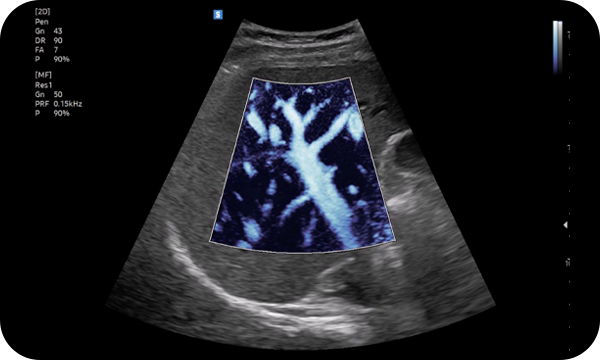

MV-Flow™ visualizes microcirculatory and slow blood flow to display the intensity in color. It is suitable for observation of microcirculatory and volume of slow blood flow.